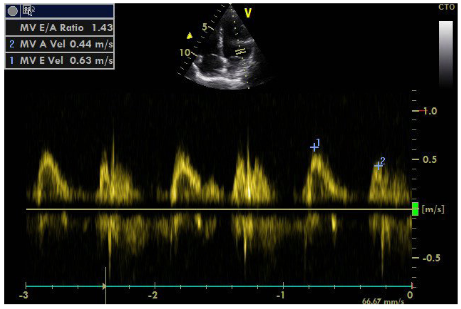

Urine test did not show albuminuria, while renal function deteriorated in the last six months: urea was increased from 25 to 49mg/dl and creatinine from 0.7mg/dl to 1.3mg /dl. In kidney ultrasound the right kidney was at 11cm while the left kidney was smaller, at 9.5cm. The triplex of the renal arteries showed a significant degree of stenosis in the left renal artery (Figures 1 & 2). The maximum velocity in doppler must not exceed 1.4 m/s while our patient has 5m/s in the left artery! Additional pathological findings are: (Figure 3)

Figure  1 Doppler of left renal artery.

An additional element is the localization of the stenosis in the initial part of renal vessel, as opposed to FMD that commonly affects the middle and peripheral portions. The sudden deterioration of renal function within a short period of time also advocates for atherosclerosis as the FMD has a slower course. It is noted that atherosclerosis may lead to complete abstraction/thrombosis over time, rarely occurring FMD. Finally, the immunological test performed to rule out vasculitis was negative. Renal arteriography indicated a 99% stenosis to the left and the patient underwent a successful stent implantation. After angioplasty, blood pressure returned to normal and the patient did not receive any medication. It is worth noting that despite the presence of stage III hypertension and the underlying disease, the patient did not show signs of diastolic dysfunction in the Doppler (Figures 8–10), nor any signs of hypertrophic left ventricle in ECG.  Not a patient with long-standing uncontrolled hypertension. Moreover, to stress echocardiography with doboutamine there were no wall motion abnormalities, while coronary flow reserve was normal (CFR LAD=2.2) (Figure 11A & 11B).

Figure  7 Doppler of mitral valve inflow.